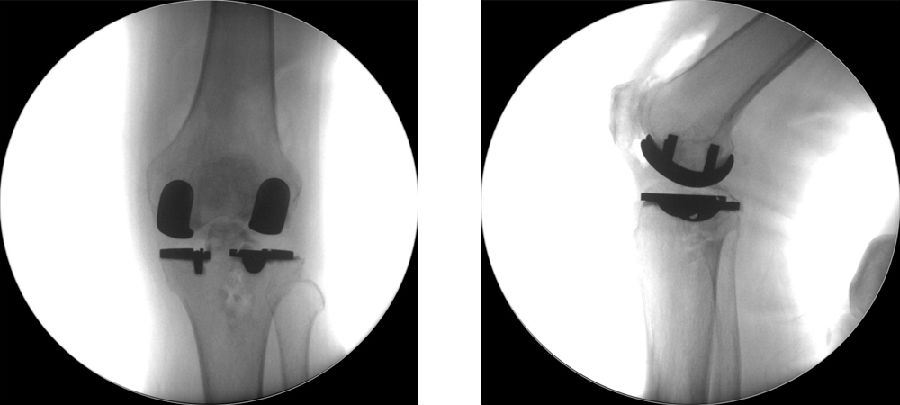

术后透视。A.正位B.侧位

术后1周X-ray片

理想假体位置 A.股骨假体 胫骨假体中心线一致;B.股骨假体固定栓与后侧皮质呈35-40°

理想假体位置即前缘平稳过渡,后缘包容很好且不超出。